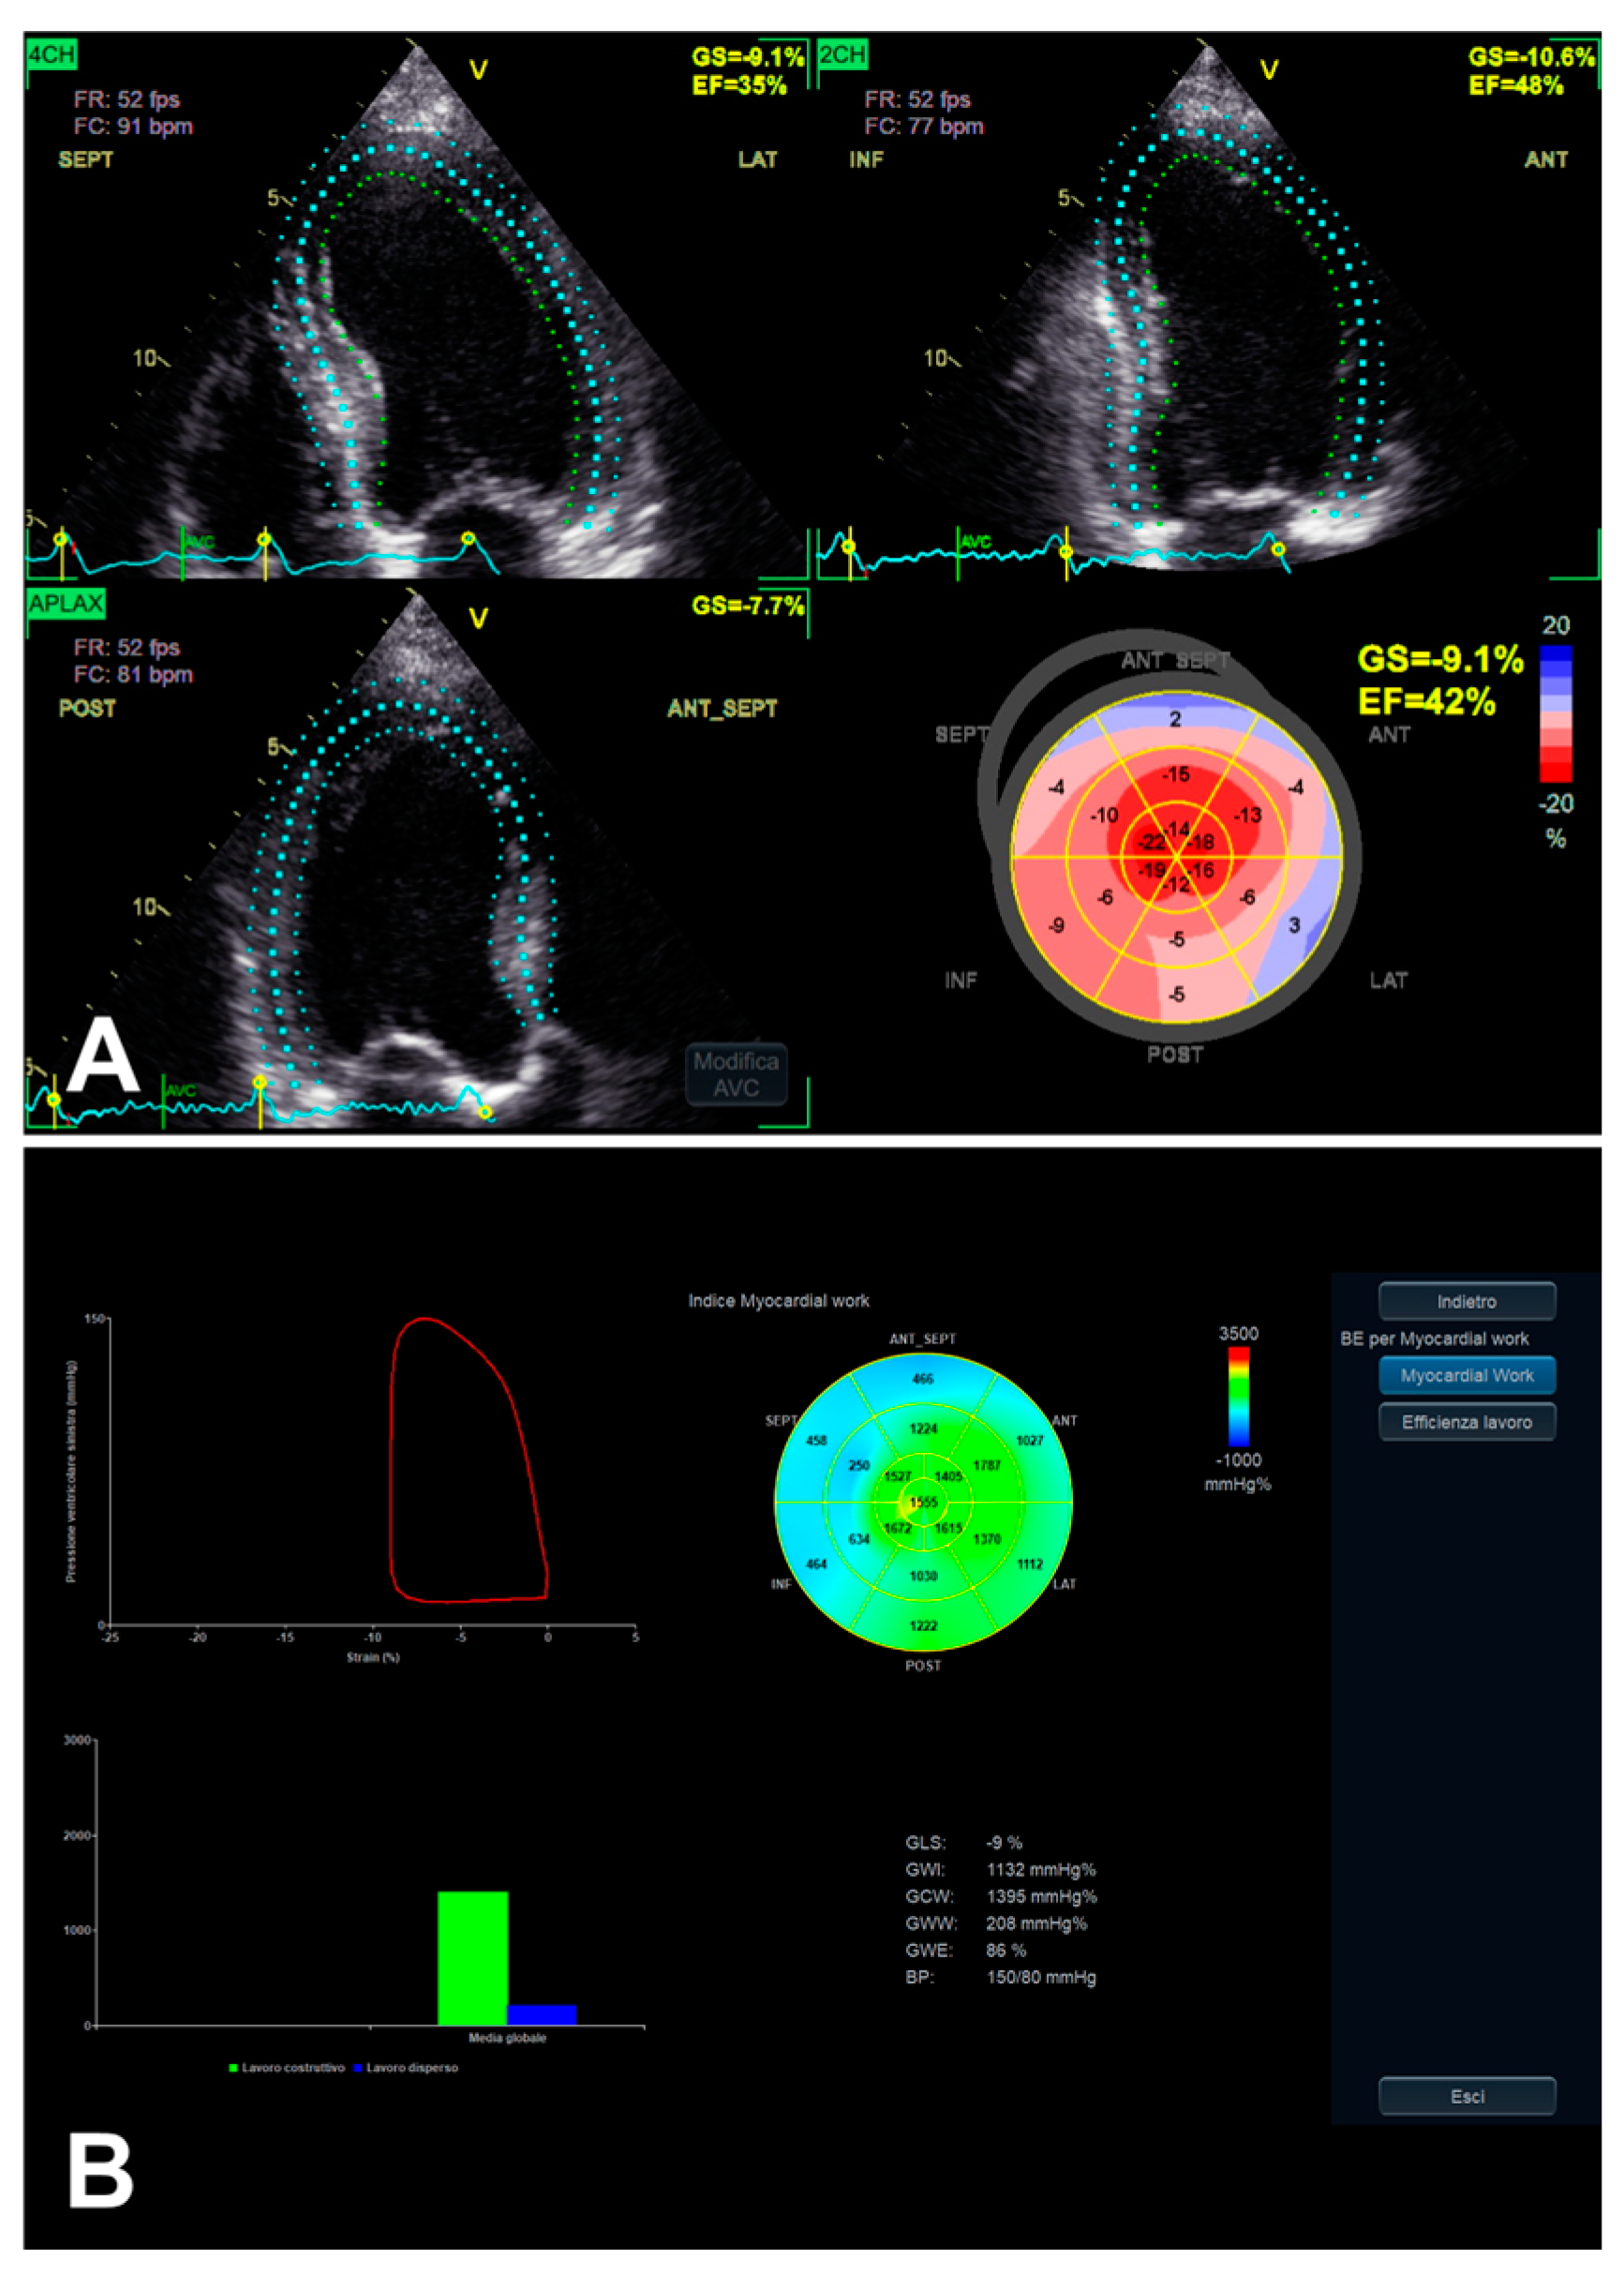

3.3. Left Ventricular Myocardial Work

| Parameter | Views/MWi | Technique/MWi Definition | Advantages | Limitations |

|---|---|---|---|---|

| LV GLS | 2D apical 4C, 3C, and 2C views | Probe in apical zone with 4C, 3C, and 2C views | - Prognostic/predictive value. | - Age and load dependency; - Chest shape dependency; - Image quality-related; - Intervendor and intersoftware variability. |

| LA strain | 2D apical 4C and 2C views | Probe in apical zone with 4C and 2C views | - Prognostic/predictive value. | - Age and load dependency; - Chest shape dependency; - Image quality-related; - Intervendor and intersoftware variability. |

| LV MW | GCW | Positive work evaluated from AVO to AVC and negative work from AVC to MVO | - Relatively low intra and inter-observer variability (if good US window). | - GLS-related limits (including image quality); - AP measurement-related limits; - Single available software. |

| GWI | Total work evaluated from MVC to MVO | |||

| GWE | GCW/(GCW + GWW) | |||

| GWW | Positive work evaluated from AVO to AVC and negative work from AVC to MVO |